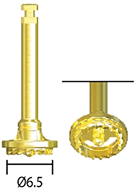

Костный пакер

SABC01